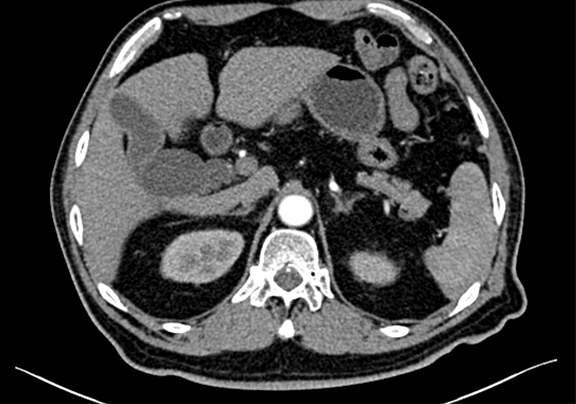

术前CT检查:动脉期